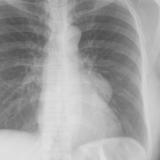

Normal pericardium

Date: 03/17/2004

Views: 4948